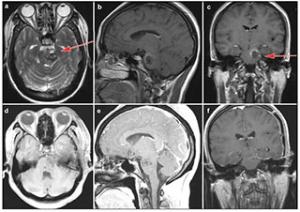

20170712151506 Figure 5 Case 3: Cavernous malformation in the left pons and lower midbrain. T2-weighted (a), enhanced sagittal T1-weighted (b) and enhanced coronal T1-weighted (c) demonstrated the location of the cavernous malformation. Enhanced axial T1-weighted (d) and sagittal T1-weighted (e) postoperative within 72 hours showed that the lesion was totally resected. Enhanced coronal T1-weighted (f) showed no recurrence after 3 months follow-up. Red arrow showed the entry approach (subtemporal approach).